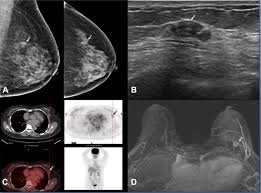

Fdg Pet Pet Ct And Breast Cancer Imaging Radiographics from pubs.rsna.org A breast pet scan is often very specific and sensitive and is approved for patients. It's an effective imaging test for finding cancer and learning its stage. Bone scans, positron emission tomography (pet), and computed tomography (ct) all continue to be employed alone or in combination for the detection of breast cancers suspected to have spread. Breast positron emission tomography (pet) scan is an imaging test that uses a tracer (radioactive substance) to look for symptoms of breast cancer. Pet scan is a type of test that may be used in cancer treatment. Pet scans can be used to determine how much cancer is in a person's body and how far the cancer has spread, which is called staging. It can be done along with a ct scan. Pet scans can be useful for evaluating people after breast cancer has already been diagnosed, in a number of different ways:

The test has only a limited ability to detect small tumors. Pet scan for breast cancer a positron emission tomography (pet) scan is an imaging test that uses a radioactive substance (called a tracer) to look for potential spread of breast cancer. In some instances, cancers may not show on the scan. Combining a pet scan with an mri or ct scan can help make the images easier to interpret. Pet scans can be used to determine how much cancer is in a person's body and how far the cancer has spread, which is called staging. This tracer can help identify areas of cancer that an mri or ct scan may miss. With cancer cells, they appear as bright spots due to its higher metabolic rate compared to normal cells. However, the pet scan uncovers every unusual activity in the body and is more sensitive than any other existing imaging test. Pet/ct scan can accurately localize lymph node metastasis and help to monitor the response to chemotherapy. Breast positron emission tomography (pet) scan is an imaging test that uses a tracer (radioactive substance) to look for symptoms of breast cancer. Pet scans can also help to assess whether metastatic breast cancer is responding to the treatment. Pet scans are not used to screen women for breast cancer. Pet/ct scans using axumin tracer, approved by fda last year and newly approved by medicare in some areas, are starting to be done at different locations.

Thus, pet/ct detected a primary breast mass and metastatic lymphadenopathy that mammography and ultrasonography failed to detect a finding not previously reported, to our knowledge. Mammograms take advantage of the fact that most of the female breast is fat tissue, so it's relatively transparent to the low doses of radiation used in mammography. One example is a combined pet and ct scan (known as pet/ct), available in some centers. Does anyone know if a ct scan can show breast cancer or colon cancer rather than the standard mammogram or colonoscopy? When breast cancer cancer spreads.

Mammograms take advantage of the fact that most of the female breast is fat tissue, so it's relatively transparent to the low doses of radiation used in mammography. Am wondering if all the while we are getting ct scans for lung cancer, is this also scanning for. This test can help show if the cancer has spread to your bones. Normally, a pet scan is not used for breast cancer screening. This radioactive tracer can help identify areas of cancer that an mri or ct scan may miss. In conclusion, this case shows that pet/ct can be utilized as an alternative method of diagnosing breast cancer in cases where conventional imaging modalities fail. The report of ct scan cannot be the basis of determining if a patient has cancer or not; A pet scan is often combined with a ct scan (known as a pet/ct scan). Right now, ct scans are not used routinely to evaluate the breast. This tracer can help identify areas of cancer that an mri or ct scan may not show. A breast pet scan is often very specific and sensitive and is approved for patients. Objectives bone is the most frequent site of breast cancer metastases.considering many breast cancer patients are old age,bone is likely affected by degenerative or inflammatory bone disease.recently pet/ct has become an alternative study which could provide an accurate and efficient tool for detection of primary and metastatic foci.the purpose of this study was to compare the accuracy between pet/ct and bone scan for detecting bone metastases in breast cancer. In a ct scan, you can see the broad pictures of all tissues and organs present in the body.